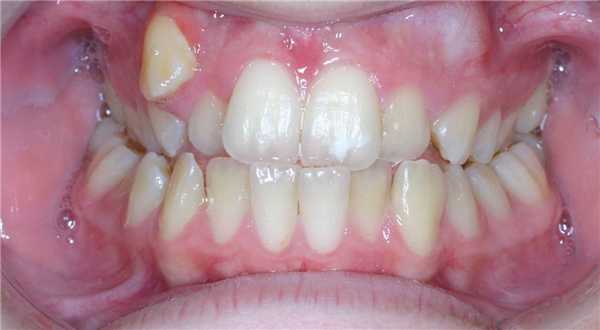

Симптомы дистопии зубов чаще всего наглядны и легко заметны. Достаточно посмотреть на положение всех элементов зубного ряда, чтобы увидеть, что некоторые из них заняли не свои места или просто растут неровно. Другие симптомы:

Ортодонт или даже стоматолог-терапевт может легко определить дистопию зуба при обычном осмотре, если аномалия не является сложной. В ряде случаев, когда элемент зубного ряда остается в десне, оказывается в небе или ином месте, во время осмотра можно только заподозрить проблему.

Если врач не нашел какой-то из зубов, который уже должен прорезаться у ребенка (или взрослого, если речь идет о восьмерках), он направляет пациента на рентгеновское исследование. На снимке отлично видны все нарушения и можно увидеть сформированные зубы в мягких тканях. Для уточнения положения и для последующего лечения применяют артопантомографию, создание гипсовых моделей челюстей и делают телерентгенографию.

Дистопированный зуб на рентгене

Дистопированный зуб способен определить стоматолог-терапевт или ортодонт в ходе обычного клинического осмотра. Чтобы уточнить положение дистопированных зубов чаще всего применяют артопантомографию, а также изготавливают гипсовые модели челюстей и осуществляют телерентгенографию.

Дистопированный зуб можно обнаружить и самостоятельно, однако точный диагноз способен поставить только врач.

Дистопированный зуб обычно видно сразу - он выглядит неестественно из-за выпирания или развернутого положения. Мягкие ткани могут травмироваться и воспаляться, вокруг дистопированного зуба появляются язвочки, может даже выделяться гной. Иногда становится неудобно и больно принимать пищу.